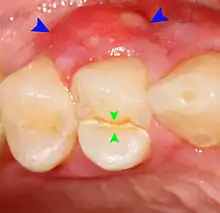

Periodontal abscesses are less common than apical abscesses, but are still frequent. The key difference between the two is that the pulp of the tooth tends to be alive, and will respond normally to pulp tests. However, an untreated periodontal abscess may still cause the pulp to die if it reaches the tooth apex in a periodontic-endodontic lesion. A periodontal abscess can occur as the result of tooth fracture, food packing into a periodontal pocket (with poorly shaped fillings), calculus build-up, and lowered immune responses (such as in diabetes). Periodontal abscess can also occur after periodontal scaling, which causes the gums to tighten around the teeth and trap debris in the pocket.[24]: 444–445 Toothache caused by a periodontal abscess is generally deep and throbbing. The oral mucosa covering an early periodontal abscess appears erythematous (red), swollen, shiny, and painful to touch.[25]

Decay (green) with apical abscess (blue)